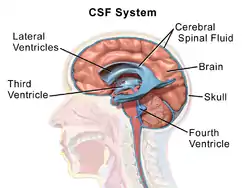

The cerebrospinal fluid circulates in the subarachnoid space around the brain and spinal cord, and in the ventricles of the brain. | |

Image showing the location of CSF highlighting the brain's ventricular system | |

There is about 125–150 mL of CSF at any one time.[1] This CSF circulates within the ventricular system of the brain. The ventricles are a series of cavities filled with CSF. The majority of CSF is produced from within the two lateral ventricles. From here, CSF passes through the interventricular foramina to the third ventricle, then the cerebral aqueduct to the fourth ventricle. From the fourth ventricle, the fluid passes into the subarachnoid space through four openings – the central canal of the spinal cord, the median aperture, and the two lateral apertures.[1] CSF is present within the subarachnoid space, which covers the brain and spinal cord, and stretches below the end of the spinal cord to the sacrum.[1][2] There is a connection from the subarachnoid space to the bony labyrinth of the inner ear making the cerebrospinal fluid continuous with the perilymph in 93% of people.[3]